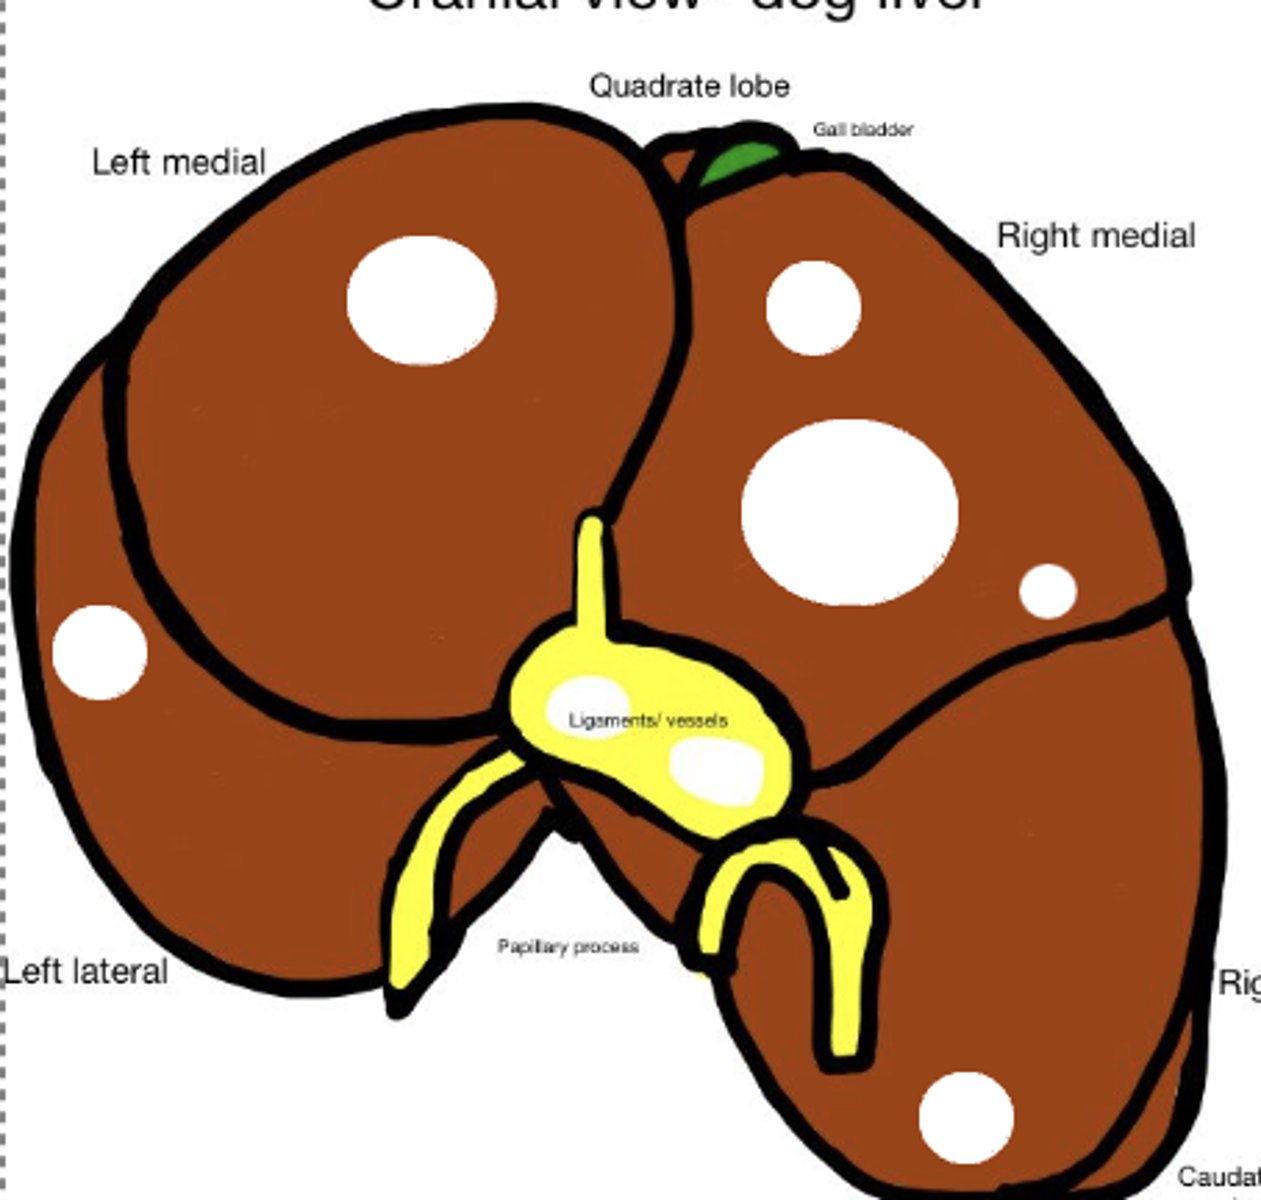

Nodular hyperplasia

-benign tumor - encapsulated

What has caused this gross appearance of this liver?

Hepatocellular adenoma

-discrete masses

-benign epithelial tumor

What has caused this gross appearance of this liver?